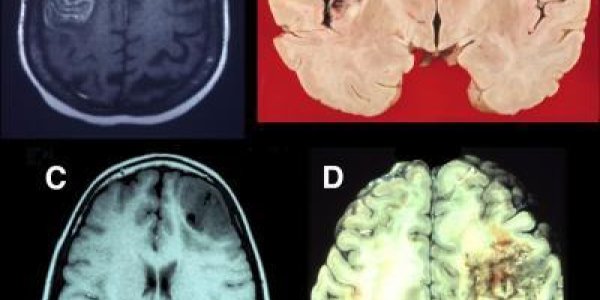

Studying Prefrontal Lobe Damage Unlocks Brain Mysteries

Until the last few decades, the frontal lobes of the brain were shrouded in mystery and erroneously thought of as nonessential for normal function—hence the frequent use of lobotomies in the early…